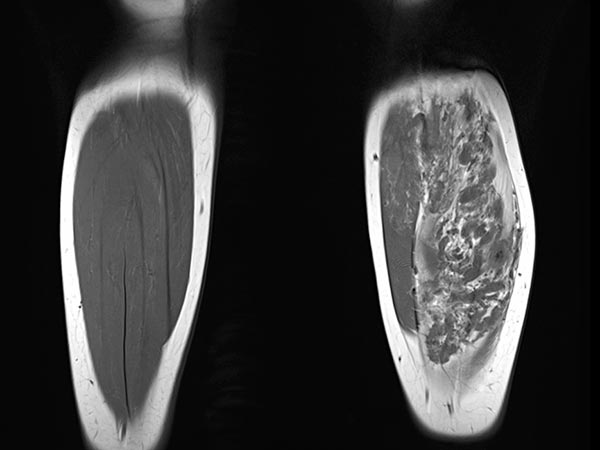

Coronal T1-weighted non-enhanced MRI shows an intramuscular, vascular lesion (isointense to the muscle) with marked interstitial hyperintense adipose tissue. This fatty tissue is more pronounced than would be usual in a normal venous malformation.

Axial T2-weighted MRI of the left lower leg shows multiple dilated, dysplastic veins in a venous malformation throughout the superficial flexor muscles. Slow flow causes stasis of the blood within the malformation with the formation of fluid-fluid levels. Almost the entire muscle consists of malformation and fatty tissue. Also visible is a large thrombus in a dilated, dysplastic vein.

In coronal, non-enhanced T1-weighted control MRI, the vascular component of the lesion is less conspicuous. However, clearly additional soft tissue remains that is pathologic (“salt-and-pepper pattern”). This tissue consists in part of hyperintense adipose tissue and in part of hypointense connective tissue. This is the typical MRI appearance of a fibro-adipose vascular anomaly (FAVA).

The vascular channels are largely occluded on axial control MRI in T2-weighted images. However, after successful occlusion of the vascular channels, a black-and-white “salt-and-pepper” pattern typical of FAVA remains. This consists of adipose tissue (hyperintense) and connective tissue (hypointense).